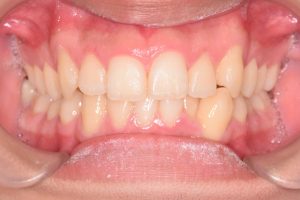

2期治療開始時(2023年7月)と装置撤去時(2025年9月)の写真です。

正面